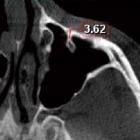

Protrusion of

the infraorbital canal into the maxillary sinus: A cross-sectional study in Cairo, Egypt: Fig. 3. Axial cone-beam computed tomographic image shows the horizontal suspension of the infraorbital canal with a displayed septal length of 3.6 mm, denoting a class II canal (septal length >3 and ≤7 mm).